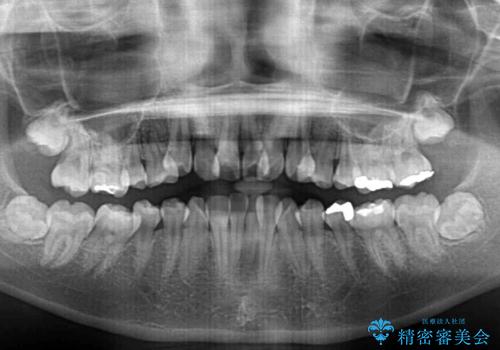

- 上下前歯のデコボコと、それによる磨きづらさを気にして来院された患者様です。

叢生解消のため、上下左右第一小臼歯4本を抜歯し、ワイヤー装置にて矯正治療を行うこととしました。